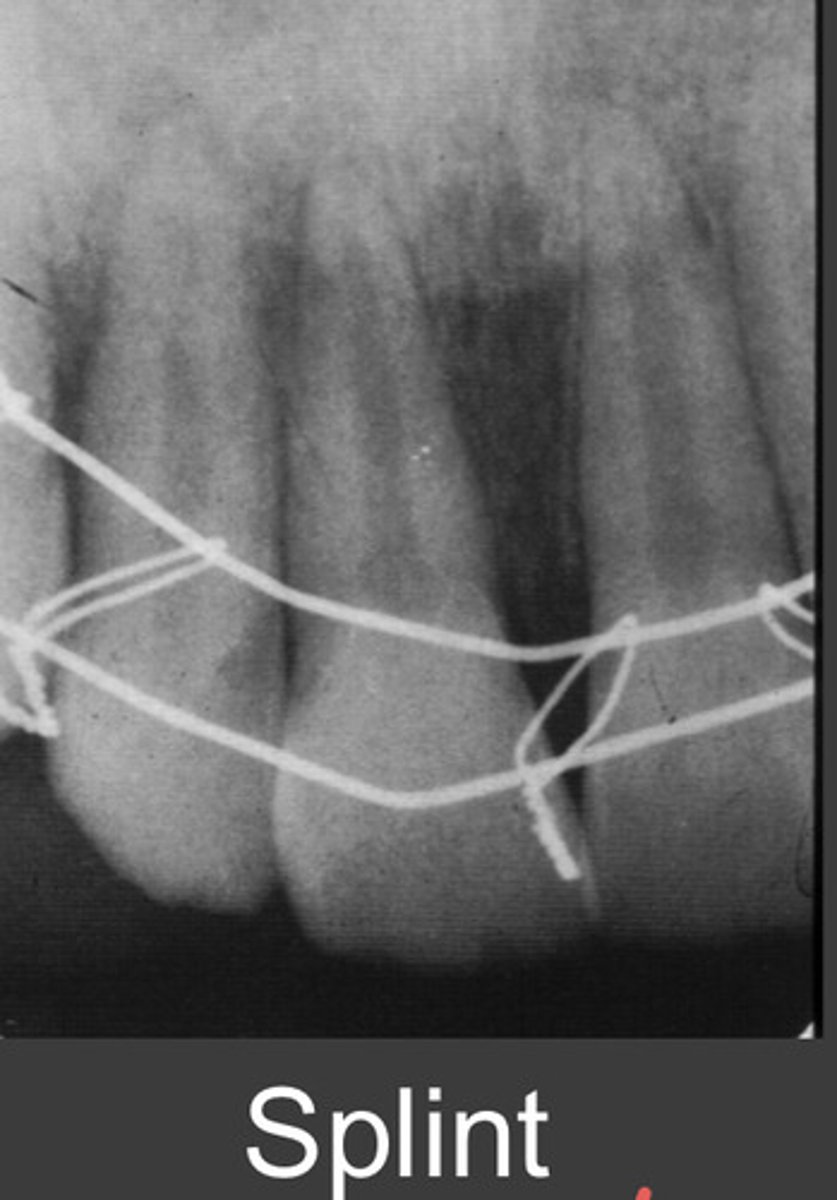

splint